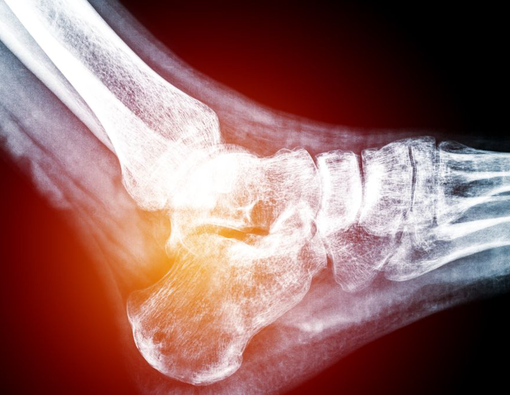

- Rontgen kaki untuk mengecek struktur tulang kaki

Nyeri tumit adalah rasa sakit yang umumnya dirasakan pada bagian belakang dan bawah kaki, yang disebut sebagai tumit.

Penyebab Nyeri Tumit

- Plantar Fasciitis (peradangan pada urat telapak kaki)

- Pembentukan osteofit

- Pengapuran tumit

- Fraktur (patah tulang)